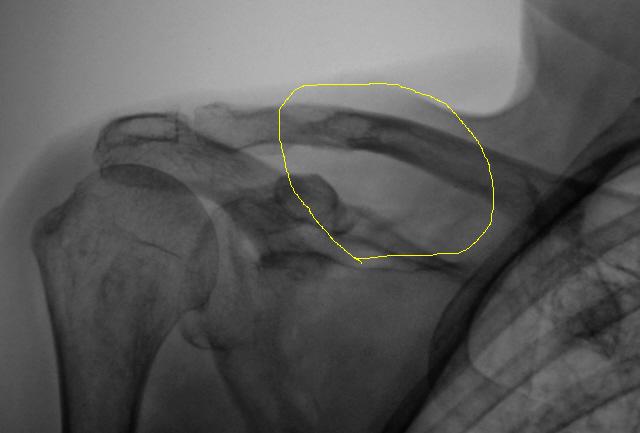

Спасибо Андрей Юрьевич. Я понял, что наиболее правильнее считать, что надостной ямы фактически нет, она полностью разрушена, как и разрушен верхний край лопатки,  осталась одна лопаточная ость, а именно её "зависшие остатки" и инфильтративный рост распространился на ключицу.

ИзображениеИзображение

Можно предположить, что обведенное "желтым", участок инфильтрированный опухолью?

Отправили в онко-диспансер. Взяли. Предварительно сказали - "Наше".